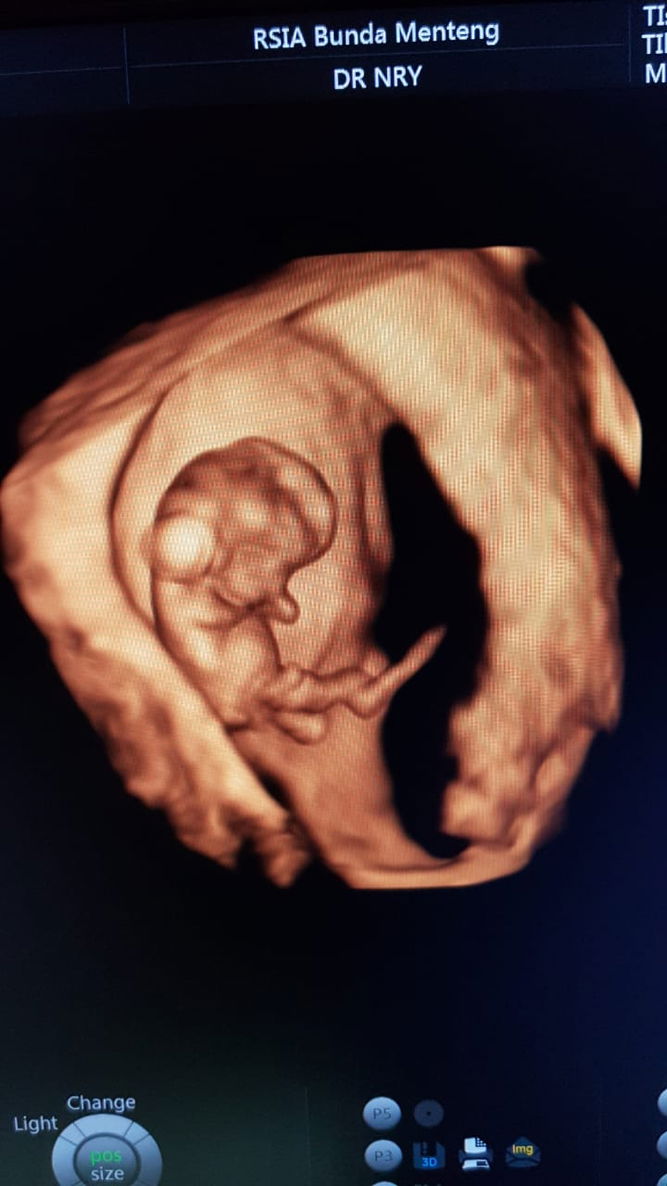

Peanut Butter

Maashaa Allah tabarakallah... Welcomeback my peanut butter ??. Sehat terus diperut mama y nak??. semoga jadi anak soleh/soleha nak. Buat bunda yg masih menanti kehadiranya, tetapberushaa & berdoa krn Allah selalu tepat waktu memberikan yg kita butuhkan. 7,5tahub penantian setelah kemarin kami kehilangan anak pertama kami di usia 6w. semangat bunda n doakan kami ya semiga sehat n lancar begitupun bunda..aamiin yaa mujibassaillin..?